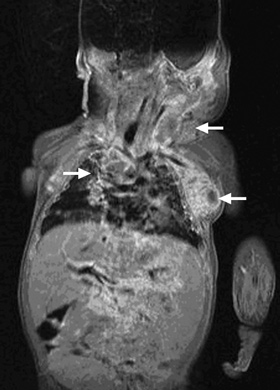

At 6 weeks of age, while still in hospital, the infant developed a 1 cm brown–pink macular lesion on the left side of the neck, and was noted to have an enlarged (1.5 cm) left axillary lymph node. Empirical antistaphylococcal therapy was introduced without any apparent effect. Biopsy of the lymph node was planned, but before this could be performed, the lymph node became acutely more enlarged, and the infant’s condition deteriorated rapidly. He developed severe respiratory distress and required re-intubation. A large mediastinal lymph node mass was noted on chest x-ray and magnetic resonance imaging (Box 1), and bronchoscopy showed extrinsic compression of the trachea and bronchi at the level of the carina.